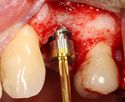

يتم اجراء جراحة الأسنان في العيادة تحت ظروف معقمة، من قبل طبيب أسنان متخصص في زراعة الأسنان و/أو جراحة الفم والفك. يتم تخدير المريض بواسطة حقنة بمخدر موضعي في منطقة دواعم السن، كما هو الحال في علاجات الأسنان العادية (في بعض الأحيان هناك حاجة بتوسيع نطاق التخدير، وفقاً لموقع الغرسات).

اذا كان العظم على استعداد لتلقي الزرع (أحيانا بعد سلسلة علاجات مسبقة)، يمكن البدء بعملية زرع الاسنان. يتم تثبيت المسامير المعدنية اللولبيه براغي، بعظم الفك. في سلسلة اخرى من العلاجات بعد فترة من ادخال البراغي، تبدا عمليات اعادة البناء عن طريق أخذ القياسات وانشاء التاج/الجسر. عندما يدور الحديث عن فترة الانتظار بين تركيب الغرسات وبين تنفيذ الاستبناء النهائي، فان هنالك اكثر من نهج واحد. النهج المتبع غالبا هو الانتظار لمدة 6 أسابيع على الأقل حتى تلتئم الانسجة، وأحيانا تصل فترة الانتظار لعدة شهور.